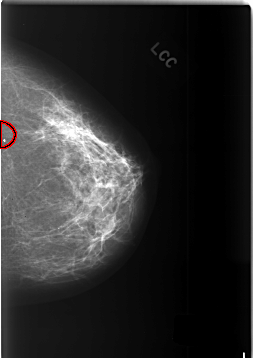

C_0381_1.LEFT_CC

FILE: C_0381_1.LEFT_CC.OVERLAY

TOTAL_ABNORMALITIES 1

ABNORMALITY 1

LESION_TYPE CALCIFICATION TYPE LUCENT_CENTERED DISTRIBUTION LINEAR

ASSESSMENT 2

SUBTLETY 5

PATHOLOGY BENIGN

TOTAL_OUTLINES 1

BOUNDARY